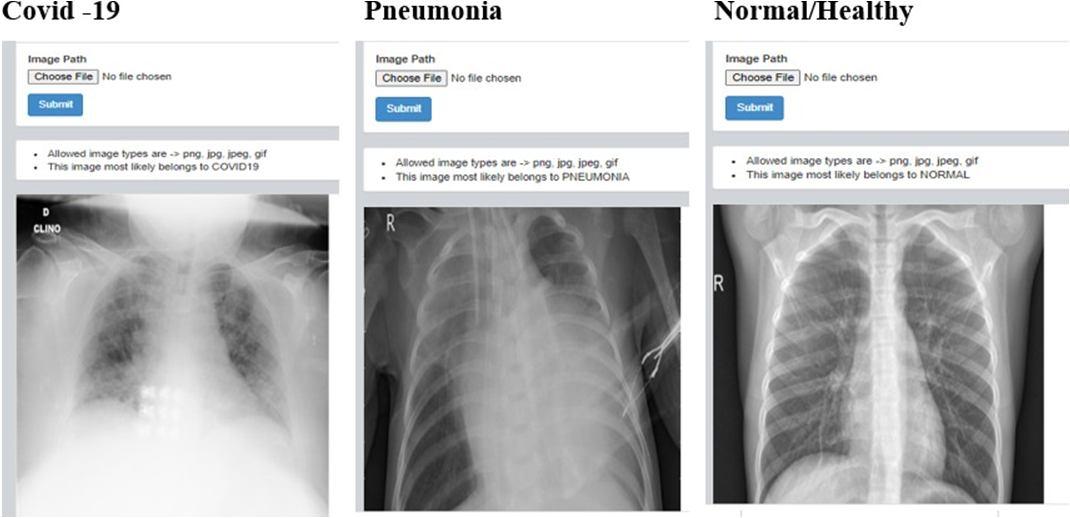

G. Results of web application

1) Detection of Covid 19 , Pnuemonia and Healthy chest x ray: Here the X ray images are fed by clicking on choose file in dash board after that we need to select file in which the images are present and upload it once after uploading needto click on submit button once after the submiting image we can observe result whether the given X ray belong to covidor pneumonia or normal.The same procedure is followed for many iteration to check whether develop web application is accurate by feeding different types of X ray images.

Fig. 17: Iteration 1

Fig. 18: Iteration 2 Fig. 19: Iteration 3 Fig. 20: Iteration 4